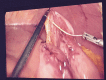

Summary: The unusual case of a 54year old female presenting with recurrent episodes of postprandial pain 2 years after LRYGP is reported. Previous radiological and endoscopic investigations did not reveal any abnormality and after the most recent clinical presentation, a laparoscopic exploration was performed. A protruding fish bone at the biliary-digestive junction was discovered intra-operatively and successfully extracted. Dense adhesions between the involved intestinal loops were lysed in an attempt to improve intestinal transit and subsequently relieve post-prandial pain.